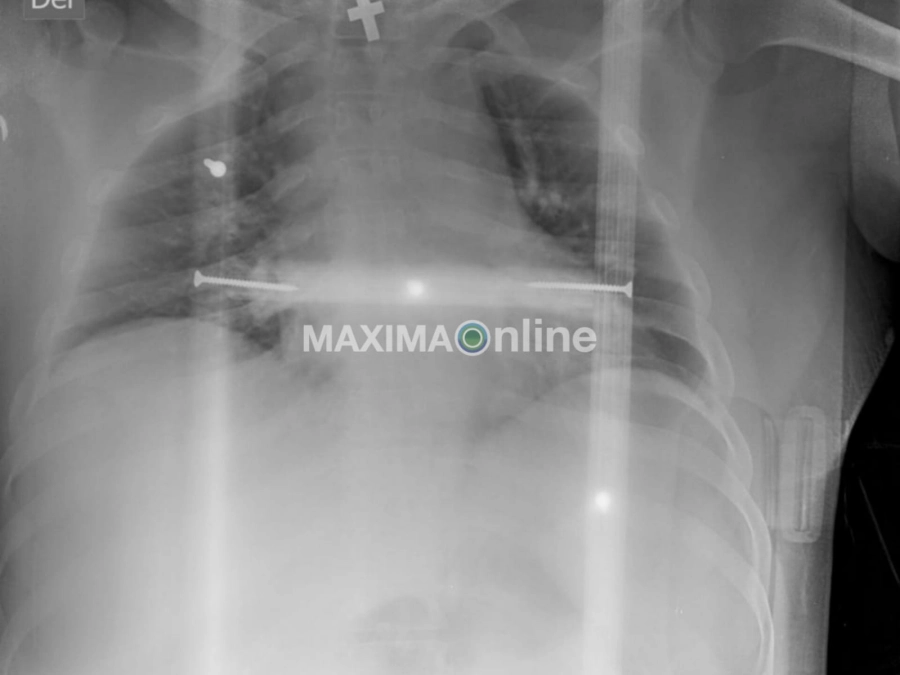

En la tragedia, Christian Claus, que conducía uno de los vehículos, sufrió fractura de fémur “y tiene la muñeca izquierda prácticamente desarmada, tiene un clavo en la pierna y dos placas en la muñeca con tornillo”, según relató su hermana Andrea.